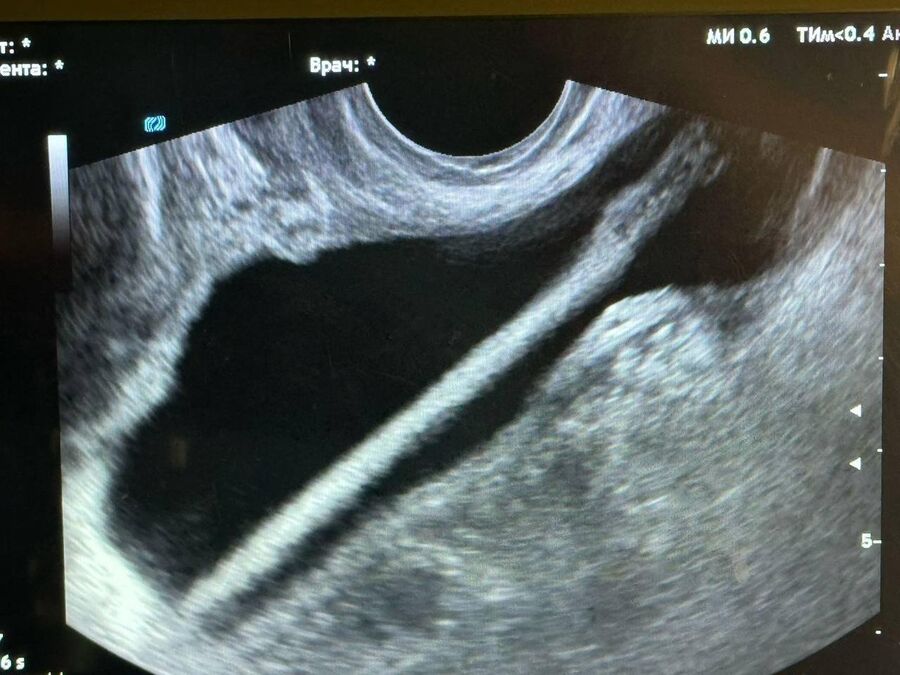

«Сперва в ходе обследования женщине было выполнено УЗИ. После врачи провели оперативное вмешательство , во время которого с помощью эндоскопа они удалили инородное тело из мочевыделительного тракта. Все прошло успешно, без каких-либо осложнений», — отметил заведующий урологическим отделением медучреждения Петр Сысоев.